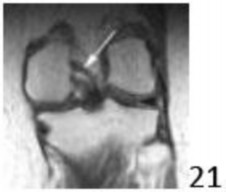

2. # Figure 21 shows a coronal T1-weighted MRI scan of the knee. The arrow indicates what anatomic structure?

DISCUSSION: The arrow is pointing to the meniscofemoral ligament. The meniscofemoral ligament connects the posterior horn of the lateral meniscus to the intercondylar wall of the medial femoral condyle. The ligament of Humphrey passes anterior to the posterior

cruciate ligament (PCL), whereas the ligament of Wrisberg passes posterior to the PCL. One or the other has been identified in 71% to 100% of cadaver knees, with the ligament of Wrisberg being more common. The PCL is shown inferior to the indicated structure. The popliteus and oblique popliteal ligament are not visualized in this image. Preferred Response to Question # 21 is 3.